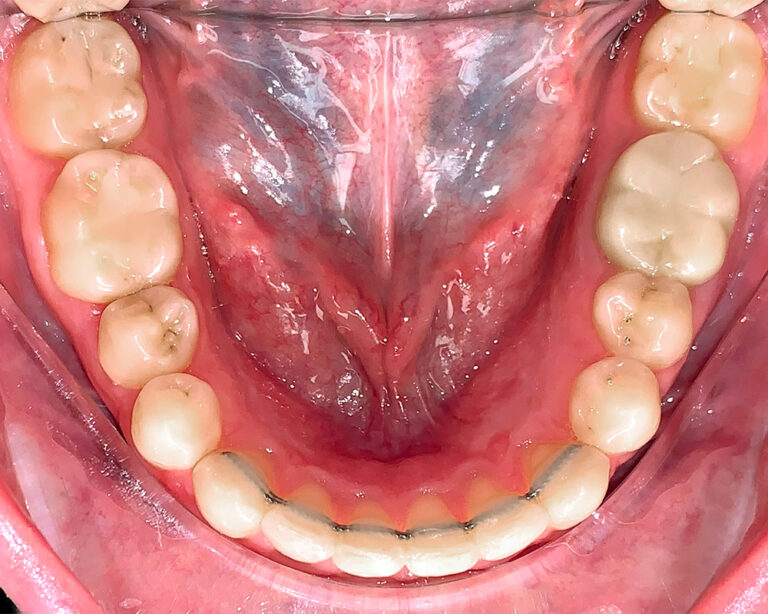

Кейс 11

Акинфиева Анна Владимировна

Количество кап ВЧ 12

Количество кап НЧ 16

ДО

ПОСЛЕ